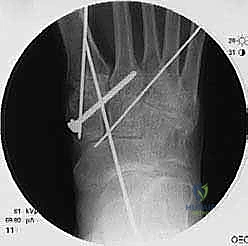

لضمان التحام العظام لتصبح عظمة واحدة صلبة، يجب تثبيتها بقوة هائلة حتى لا تتحرك أثناء فترة الشفاء. يتم استخدام مسامير معدنية متطورة (Screws)، أو شرائح معدنية خاصة (Plates)، أو دبابيس طبية متخصصة (Staples) مصنوعة من التيتانيوم الآمن على الجسم.

بعد التأكد التام من وضع العظام وثباتها باستخدام جهاز الأشعة السينية داخل غرفة العمليات (C-Arm)، يتم إغلاق الشقوق الج